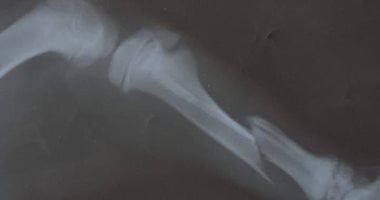

تمكن فريق من أطباء مركز طب وجراحة الحيوانات الأليفة بمديرية الطب البيطري في الغربية، من إجراء عملية لإعادة تثبيت كسر بعظام الساق اليمنى لكلب بعمر 3 أشهر تعرضه لحادث سيارة.

وتم استقبال الكلب في العيادة وتبين إصابته بكسر في عظام الساق اليمني بعد تعرضه لحادث سيارة.

وقام  بإجراء العملية الفريق المكون من الدكتورة سحر الشافعى، والدكتورة مروة نافع، والدكتور محمد الخولى، ويتم المتابعة والتأكد من استقرار الوضع الصحي للحالة بعد العملية الجراحية وتقديم العلاج اللازم مع توقعات بعودته إلى حياته الطبيعية والتعافى في وقت قريب.